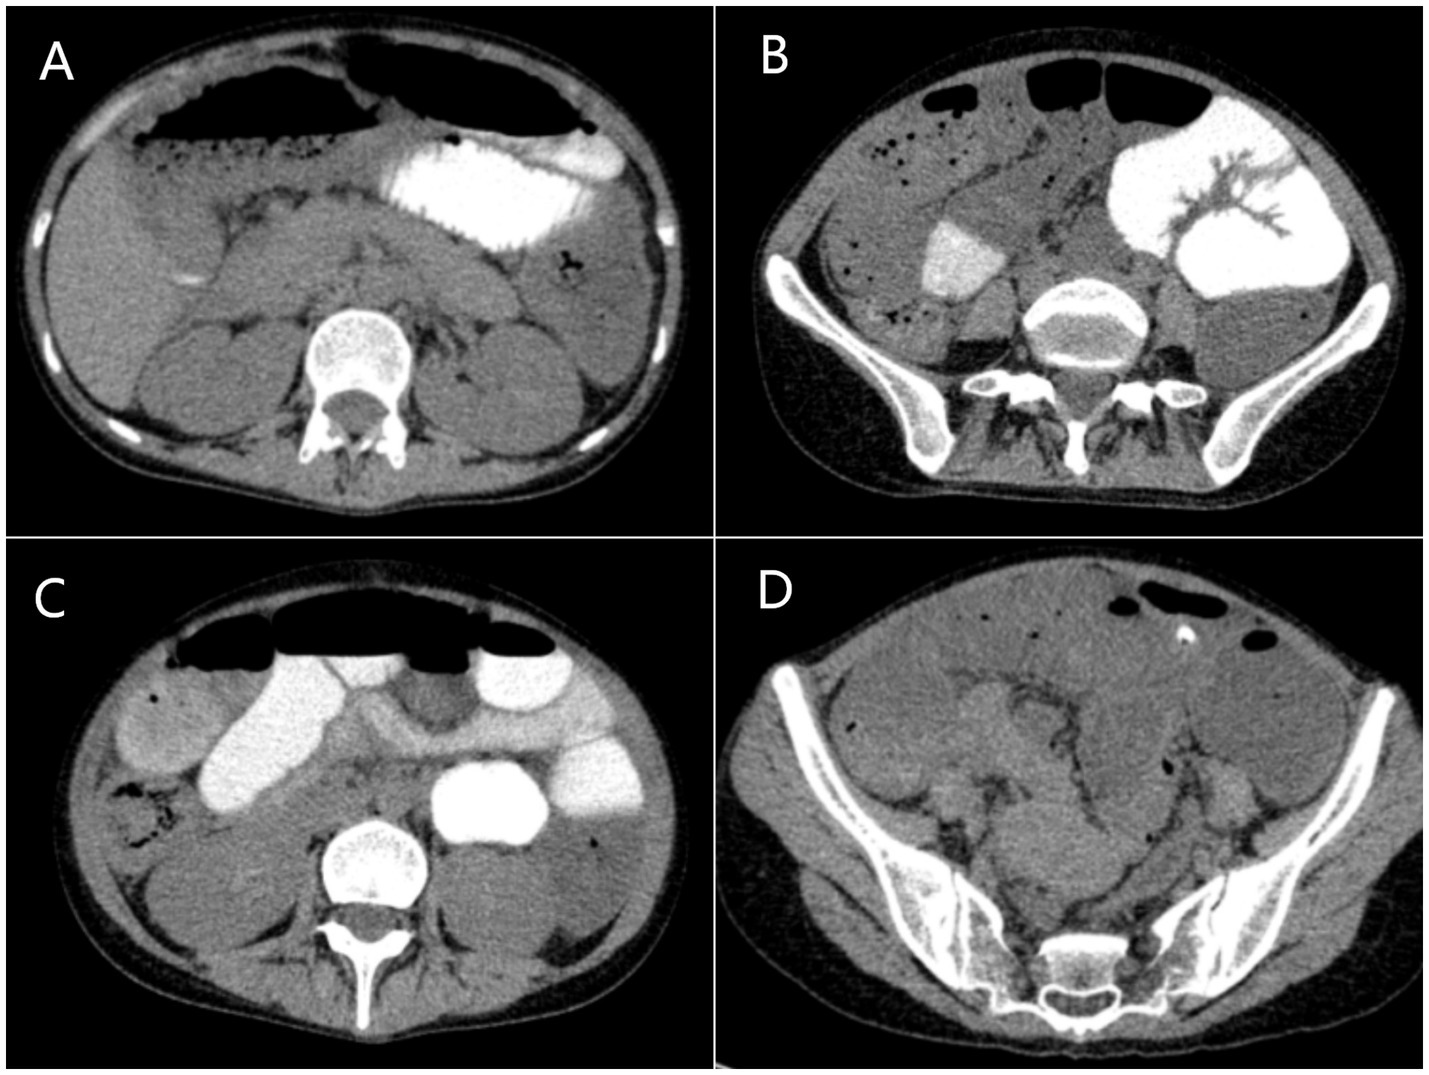

Gastrointestinal obstruction: On July 14, 2025, the patient developed the first episode of bowel obstruction, with severe abdominal distension and reduced bowel sounds at 1 per minute. An abdominal X-ray in the upright position showed gas accumulation and bowel dilation, observed during gastrointestinal tube placement (Figure 4). CT scan revealed air-fluid levels in part of the small bowel. Abdominopelvic CT showed diffuse small bowel dilatation with air–fluid levels without an identifiable transition point or mechanical obstructing lesion, and there was no imaging evidence of volvulus, hernia, or mass. After gastrointestinal decompression, enteral nutrition was administered, and the patient’s condition improved. She gradually resumed a liquid diet and then a normal diet, while continuing treatment for MELAS. Despite this, the patient experienced a second episode of bowel obstruction from August 20 to August 23, 2025, with progressive abdominal distension, absence of gas or stool passage, abdominal pain, nausea, and vomiting. Repeat CT again demonstrated marked bowel dilatation with air–fluid levels without a definite transition point or obstructing lesion, supporting the diagnosis of acute intestinal pseudo-obstruction rather than mechanical obstruction. (Figure 5). The patient was unable to take oral anticonvulsant medications, so diazepam was administered intravenously via a micro-pump. A nasogastric tube was inserted for decompression, and a small-bowel decompression tube was placed under interventional guidance (Figure 6). After 12 days of treatment with enema, enteral and parenteral nutrition, the patient’s bowel function gradually recovered. Bowel sounds returned to normal, and she was successfully discharged after transitioning to a normal diet. A follow-up phone call 16 days post-discharge revealed no adverse events.

Figure 5

The abdominal CT during the second episode of bowel obstruction. (A–D) Axial scans showing gas accumulation and bowel dilation in the small intestine.

In addition to stroke-like episodes, acute intestinal pseudo-obstruction (AIPO) is an uncommon manifestation of mitochondrial encephalomyopathy. Intestinal pseudo-obstruction, first described by Dudley et al. (16) in 1958, is a disabling motility disorder characterized by severe symptoms and signs of intestinal obstruction, such as abdominal pain, distention, nausea, and vomiting, along with radiographic evidence of bowel dilation in the absence of any mechanical obstruction. While typically regarded as a small-bowel motility disorder, pseudo-obstruction can occur anywhere in the gastrointestinal tract. It can present as either an acute condition, such as Ogilvie syndrome, or a chronic, remitting, or persistent disorder. In cases of small bowel obstruction, the inability to administer oral medications complicates treatment. Seessle et al. (17) reported a case of a 26-year-old MELAS patient who developed acute paralytic ileus. Conservative treatments proved ineffective, but high-caloric parenteral nutrition through a central venous catheter resulted in rapid clinical improvement. Similarly, Nakae et al. (18) described a MELAS patient with chronic intestinal pseudo-obstruction (CIPO) who showed improvement after receiving distigmine bromide, which may work by targeting acetylcholine receptors on the interstitial cells of Cajal to enhance bowel motility. Kawano et al. (19) also reported a 51-year-old MELAS patient with CIPO whose symptoms, including nausea, vomiting, and abdominal distension, gradually improved following treatment with acotiamide. The mechanisms of intestinal dysmotility in MELAS may be linked to mitochondrial dysfunction affecting smooth muscle cells and the enteric nervous system, leading to impaired motility. Reduced mitochondrial ATP production and lactate accumulation, common in MELAS, may weaken the contractility of intestinal smooth muscle, contributing to intestinal pseudo-obstruction. Mitochondrial dysfunction may also affect the enteric nervous system, disrupting the regulation of gut motility (14). Our patient experienced two episodes of intestinal obstruction. The first episode occurred during a period of critical illness, with the patient being exposed to sedatives and systemic stress, which may have contributed to the development of paralytic ileus. To exclude mechanical obstruction, an abdominopelvic CT scan was performed, with careful evaluation for a transition point. The results showed diffuse small bowel dilatation with air–fluid levels but no obstructing lesion, no definite transition point, and no imaging evidence of volvulus, hernia, or mass. A surgical consultation was obtained, and it was determined that mechanical obstruction was unlikely. The patient was therefore managed as having acute intestinal pseudo-obstruction (AIPO). Despite initial conservative treatments, including total parenteral nutrition and gastrointestinal decompression, the symptoms showed limited improvement. After the neurological condition stabilized, and with the discontinuation of sedatives and analgesics, the second episode of bowel obstruction occurred, reinforcing that the condition was unlikely to be related to ICU-associated ileus. This recurrence of non-mechanical intestinal dysmotility, in the absence of persistent electrolyte imbalances or other ICU-related factors, further supports the diagnosis of MELAS-related intestinal involvement rather than a transient ICU-associated ileus. After jejunal decompression tube insertion, the symptoms improved. Therefore, early insertion of a jejunal decompression tube can be an effective treatment option when a MELAS patient presents with acute intestinal obstruction.